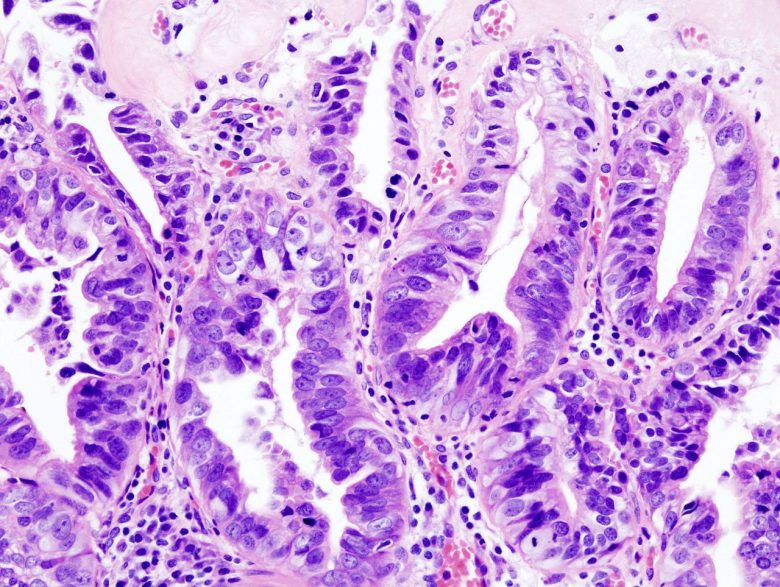

Esophageal cancer

“The most common types of esophageal cancer are adenocarcinoma and squamous cell carcinoma. These two forms of esophageal cancer tend to develop in different parts of the esophagus and are driven by different genetic changes.

“Smoking, heavy alcohol use, and Barrett esophagus can increase the risk of esophageal cancer. Signs and symptoms of esophageal cancer are weight loss and painful or difficult swallowing. Tests that examine the esophagus are used to detect (find) and diagnose esophageal cancer.”

Image Credit: Nephron / Wikimedia Commons.